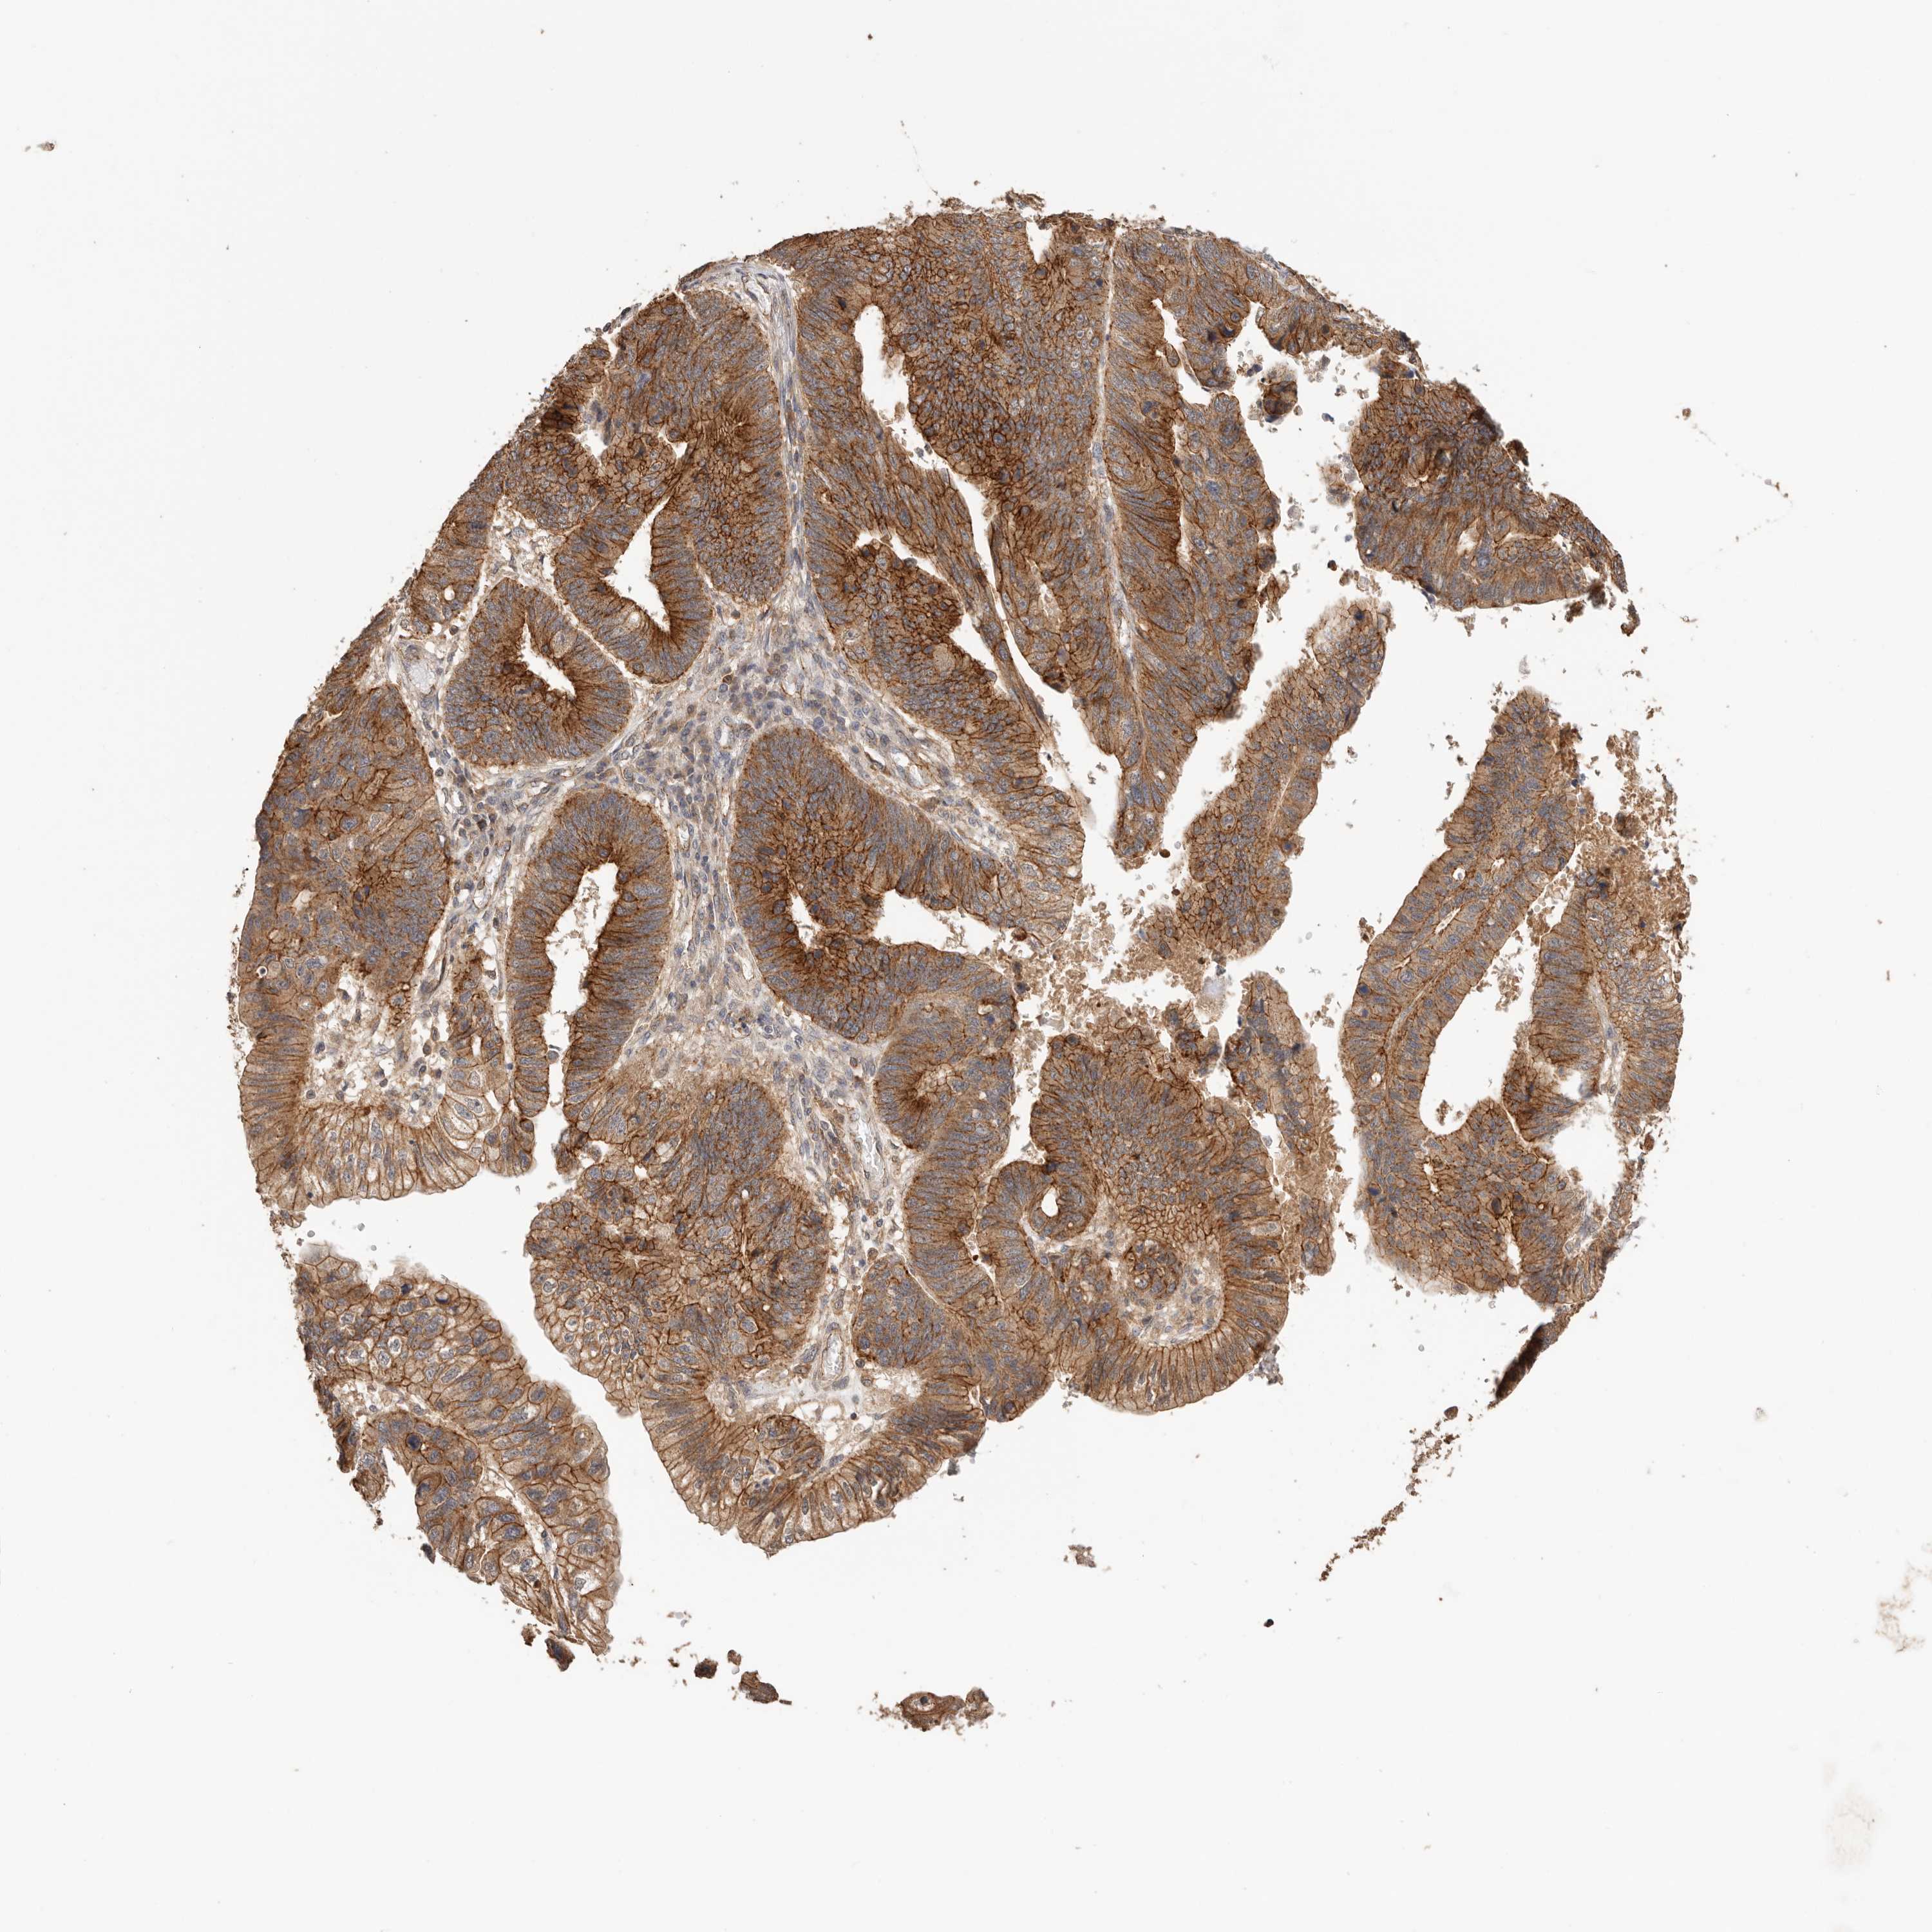

STOMACH CANCER - Protein expressioni

A mouse-over function shows sample information and annotation data. Click on an image to view it in a full screen mode. Samples can be filtered based on level of antibody staining by selecting one or several of the following categories: high, medium, low and not detected. The assay and annotation is described here.

Note that samples used for immunohistochemistry by the Human Protein Atlas do not correspond to samples in the TCGA dataset.

Antibody stainingi

Antibody staining in the annotated cell types in the current human tissue is reported as not detected, low, medium, or high, based on conventional immunohistochemistry profiling in selected tissues. This score is based on the combination of the staining intensity and fraction of stained cells.

Each image is clickable and will lead to virtual microscopy that enables deeper exploration of all samples and also displays staining intensity scores, fraction scores and subcellular localization as well as patient and tissue information for each sample.

HPA030212

HPA030213

HPA030214

HPA030215

CAB013496

Staining

High

Medium

Low

Not detected

Intensity

Strong

Moderate

Weak

Negative

Quantity

>75%

75%-25%

<25%

None

Location

Nuclear

Cytoplasmic/membranous

Cytoplasmic/membranous,nuclear

Adenocarcinoma, NOS